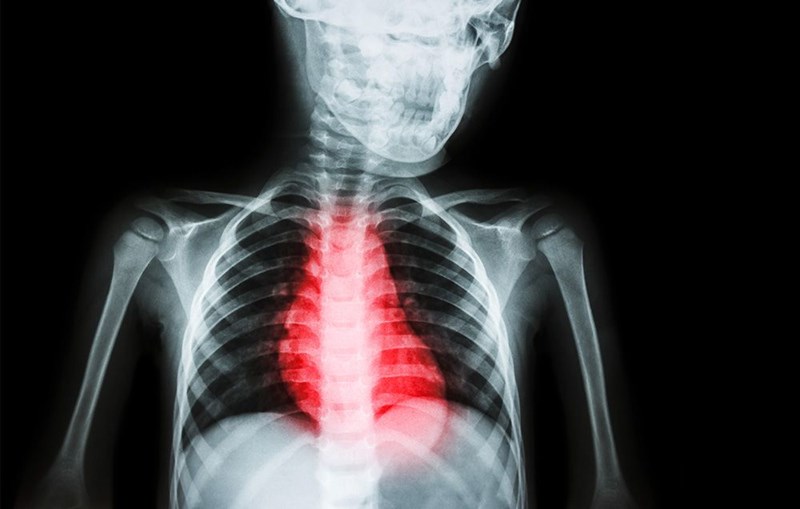

Καρδιακές παθήσεις

Οι γιατροί λένε ότι ένας από τους κινδύνους της υγείας σου εξαιτίας ανεπάρκειας καλού ύπνου είναι η υπέρταση. Πρόσφατη έρευνα της Ευρωπαϊκής Καρδιολογικής Εταιρείας έδειξε ότι οι μεσήλικες άνδρες που κοιμούνται 5 ώρες ή λιγότερο τη νύχτα διατρέχουν διπλάσιο κίνδυνο για σοβαρό καρδιαγγειακό επεισόδιο κατά τη διάρκεια των επόμενων 20 ετών από εκείνους που καταφέρνουν να ολοκληρώσουν έναν 8άωρο ύπνο.

- Η λύση: Τρέξιμο 2 έως 3 χιλιομέτρων κάθε μέρα. Ή περπάτημα 5 χιλιομέτρων.